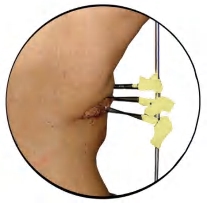

(3)然后取双股10号粗丝线用穿线导引器自肋骨下通过,再自切口的两侧软组织内穿出皮肤,连接橡皮条将其固定在颅盆装置上(图3-7)。每条肋骨均按此方法折弯固定,共做3~6条肋骨,然后分层缝合切口,放置橡皮片引流,手术结束。

图3-7 将塌陷变直的肋骨折弯变圆后,用双股10号粗丝线将3~6条肋骨提起,通过橡皮膜将其固定在颅盆牵引装置的立柱上

回病房后按颅盆牵引护理,允许早期下床活动。术后常规胸透,看有否气胸存在。练习深呼吸、吹气球以加强肺功能。术后24~48h拔除引流片,10天后拆除皮肤缝线,3周后拆除肋骨牵引线(图3-8)。等待下一步做脊柱侧弯矫形术。

A.后面观,左侧剃刀背明显,右侧胸廓严重塌陷。B.侧面观,脊柱后侧凸明显,右侧胸廓严重塌陷肋骨变直,肋前缘翘起,胸腔矢状径加大,躯干部缩短。C.胸椎后侧凸Cobb’s角186°,为脊柱侧弯患者中最大的角度。其弯曲段已形成U形襻,比180°还超过6°,为一例稀有病例。D.经颅盆牵引30天,胸椎侧凸从186°变成120°。E.继续牵引至45天胸椎侧凸变成99°。下一步先做胸廓成形术,后做脊柱侧凸弹性分叉生长棒矫形术,因为对重度脊柱弯曲只有颅盆牵引加弹性分叉生长棒的治疗方法,才能产生内支撑内固定的作用,其他内固定器械难以发挥作用。F.术前,脊柱侧凸合并重度胸廓塌陷畸形。G.经颅盆牵引后胸廓塌陷大部改善。H.将4条肋骨折弯变圆后,用粗丝线加橡皮条固定在颅盆装置的立柱上做水平牵引。I.胸廓成形术已完成,拆除牵引线后见胸廓塌陷已隆起变圆,胸腔容积加大,碳氧交换明显改善,口唇、甲床发绀消失。J.在颅盆牵引局部浸润麻醉下的卧位。K.弹性分叉生长棒的固定方法,1棒与2棒的安装,椎板下钢丝固定在1棒上,提肋钢丝固定在2棒上,两棒交替撑开,弹簧已被压缩,使两棒之间形成矩形面,使其产生生物力学稳定效应。L.内固定术后戴颅盆环早期下床活动,躯干部延长,身高增加22cm,人体重心居中,行走方便,人体外形大为改善。M.背面观